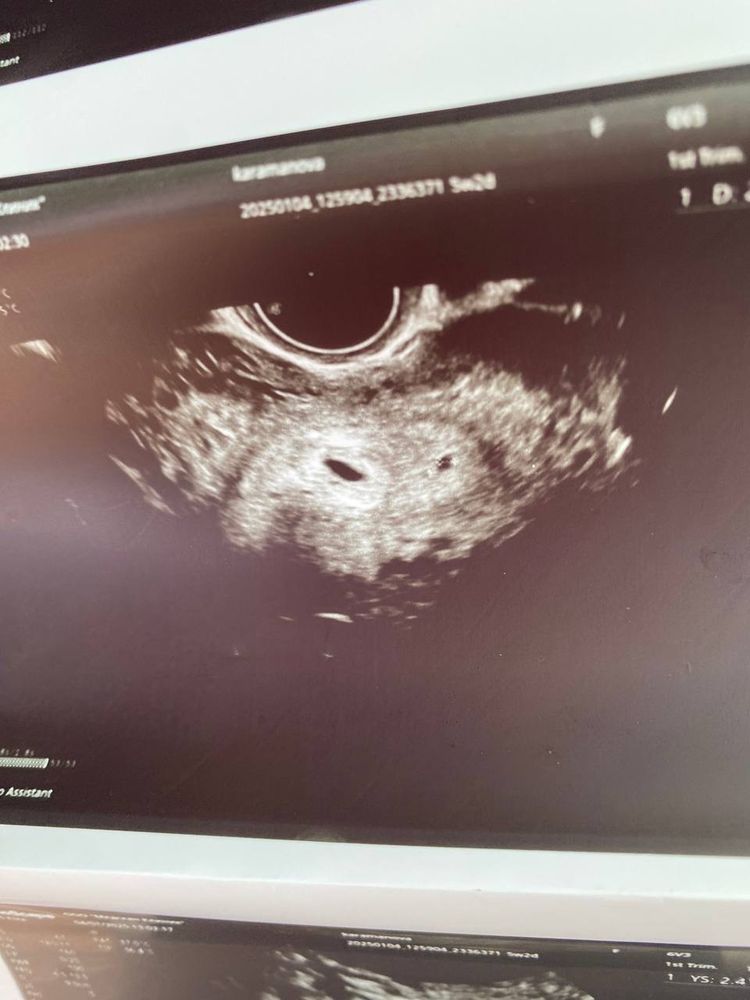

Два плодных яйца, одно гораздо меньше

Скорее всего была двойная овуляция , разница в неделю. Ещё очень рано ставить крест , ещё только 5 неделя. Всё вырастит , верьте в ваших малышей 🤗.

Разница в неделю теоретически возможна, тут только ждать, через неделю уже все понятно будет

Анастасия, может овуляция была с двух фолликулов и беременность 2 разнояйцевыми или один остановился ну тоже он же в другом пя , надо в динамике посмотреть пока еще ранний срок для выводов , расслабьтесь, отдыхайте

Анастасия, по узи не видно что 2 это пя, написано образование . Разница в неделю? Ну фиг знает. Есть некие сомнения. Но в нашей жизни может случится все.

Два плодных яйца, одно маленькое Двойня. Белок в моче, отправляют в стационар.